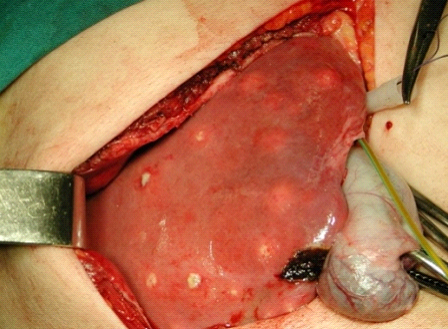

Artigo atualizado: abscessos hepáticos piogênicos

Os abscessos hepáticos são conhecidos desde a época de Hipócrates. São definidos como coleções de tecido supurativo (pus) no interior do fígado, decorrentes de infecções (no Ocidente, a grande maioria é por bactérias, que será o foco desse texto), neoplasia e iatrogenias (procedimentos médicos). Até por […]